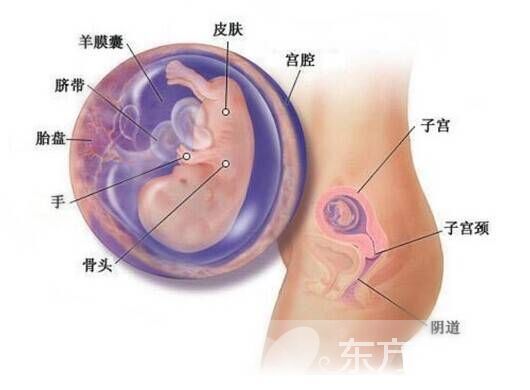

3.胎盘和脐带方面

胎盘和脐带是胎宝宝与母体联系的纽带,如果孕期有胎盘梗塞及胎盘功能不全的问题,胎宝宝就难以获得营养,不利于其生长发育。而脐带过长、过细或打结等情况同样对胎宝宝汲取营养有不利影响。